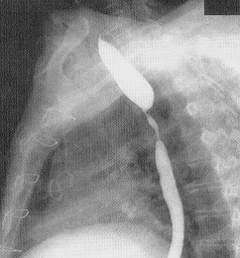

- Kontrastlı Rh-qrafiya - diaqnozu dəqiqləşdirən müayinədir.

- Rentgenoqrafik divertikul görünməsi

Kontrast məhlulunn divertikul nahiyəsində toplanması

|